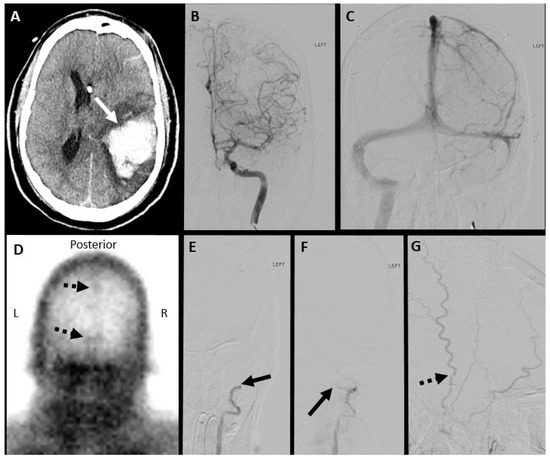

7.2. Digital Subtraction Angiography (DSA)

7.1. Nuclear Scintigraphy